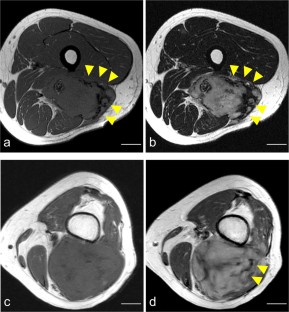

Results

PFS was significantly higher in cases with BFS than without BFS on T1WI (p < 0.01), but there was no significant difference in PFS between cases with and without BFS on T2WI. Multivariable Cox proportional hazards analysis revealed that the absence of BFS on T1WI was a high-risk factor for progression (hazard ratio, 14.9; p < 0.01). Drastic tumor regression was apparent with significantly increased low-signal area in cases with BFS on T1WI. Intra- and interobserver reliabilities of BFS on T1WI were in almost-perfect agreement (κ > 0.8).